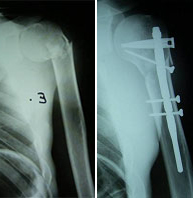

Aunque la región del hombro incluye la clavícula, el omoplato y el extremo proximal del húmero, son las fracturas de este último el grupo más importante por su frecuencia y relevancia. Las fracturas de la porción superior del húmero afectan con mayor frecuencia al paciente de edad avanzada por su menor densidad ósea y en mayor proporción al sexo femenino. En el paciente joven se asocia con traumatismos de alta energía como accidentes de tráfico y deportes de alto riesgo en los que se pueda producir un impacto directo de gran violencia como escalada, motociclismo, ciclismo, esquí, rugby, fútbol americano.

El tratamiento dependerá del tipo de fractura y grado de desplazamiento. Las fracturas desplazadas suelen ser subsidiarias de tratamiento quirúrgico. En este caso una cirugía destinada a una movilización precoz con un riesgo mínimo de complicaciones exige un gran conocimiento de la biomecánica articular así como un meticuloso manejo de los tejidos adyacentes al hueso.